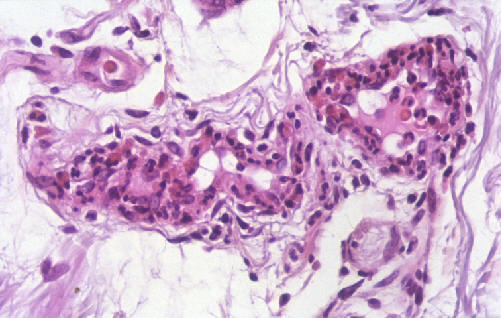

La imágen histológica de la vasculitis leucocitoclásica de

pequeño vaso se caracteriza por el edema endotelial e

infiltración de la pared vascular por polimorfonucleares con

fragmentación de los núcleos (leucocitoclasia), hemorragia y

trombosis.

La tinción de PAS revela un discreto infiltrado perivascular linfocítico y polimorfonuclear con lecucocitoclasia y depósitos de fibrina, diagnósticos de vasculitis leucocitoclástica(imagen 2: Wounds11(4):87-89, 1999)